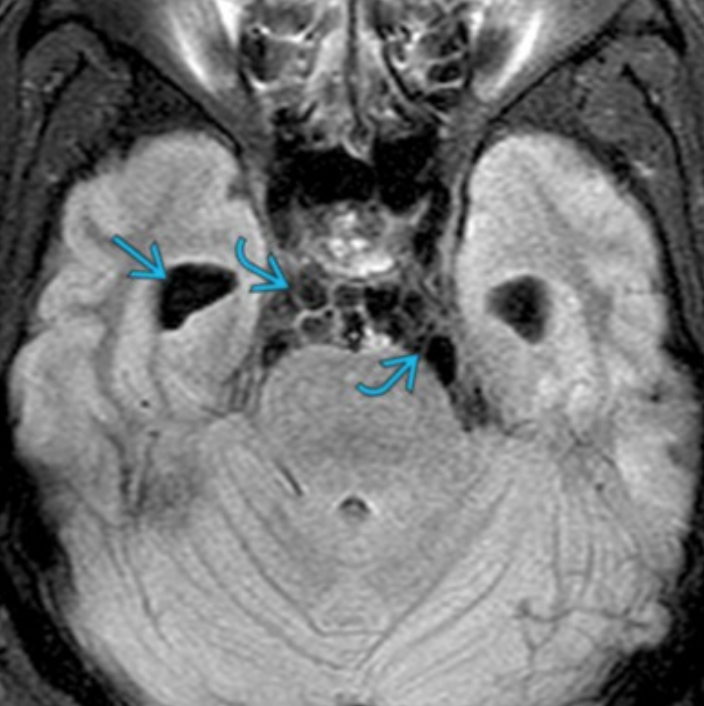

• Dilation of Peri-vascular spaces

• Dilation of perivascular spaces allows for them to merge and form large empty spaces that can then form gelatinous pseudocysts

• These gelatinous spaces are what gives the classic soap bubble finding